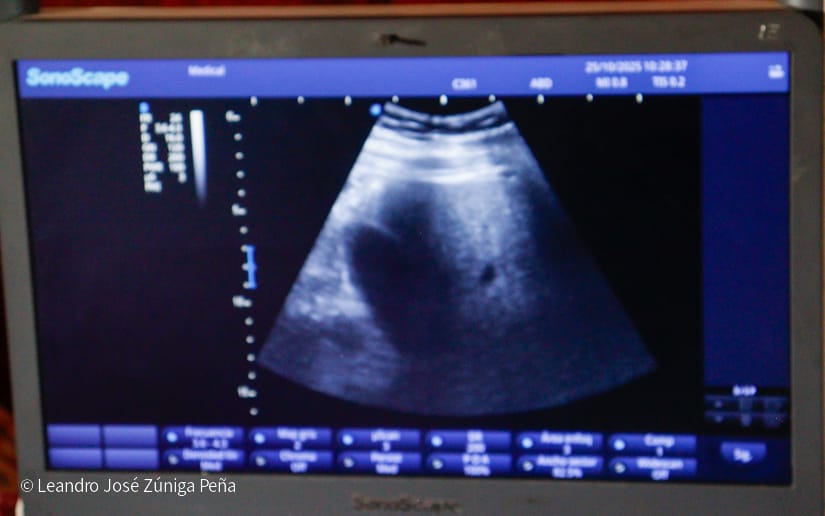

La pobladora María Solórzano Bermúdez llegó por dolencias en sus piernas, fue atendida con esmero por los médicos que orientaron un ultrasonido, fue remitida a consulta externa para ser valorada por un especialista del citado centro asistencial.